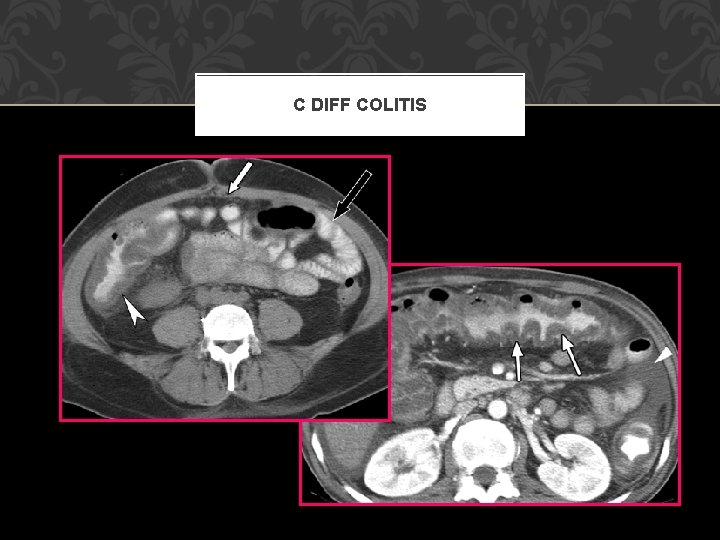

C DIFF COLITIS

GASTROINTESTINAL COMPLICATIONS GI Bleeding From any source get detailed history, place NG tube Etiology: Cushing’s ulcer (less common with PPI use) Pseudomembranous colitis Superinfection with C difficile due to alteration in normal flora Toxic colitis is a surgical EMERGENCY (mortality 20 -30%)